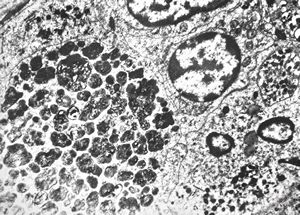

M,62y. | bone marrow - plasmocytoma

M,64y. | bone marrow - plasmocytoma

bone marrow … plasmocytoma (parafin-embedded sample)